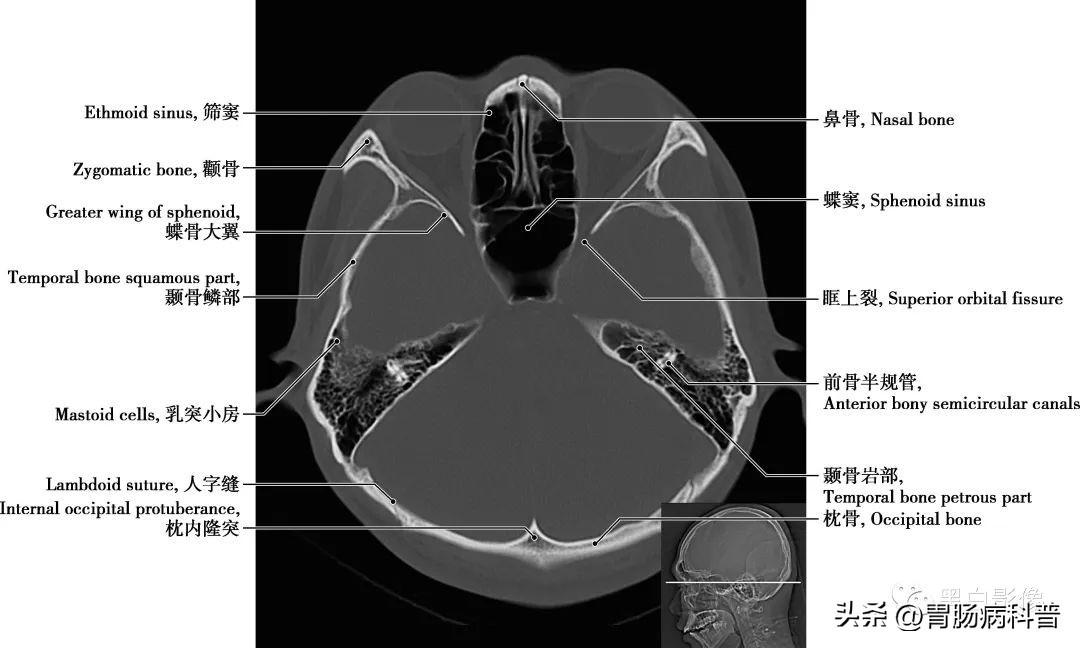

(二)骨窗轴位解剖图

图1-2-13 经海绵窦轴位切面

蝶骨大翼 由蝶骨体部平伸向两侧,继而上翘,可分三个面,脑面位于颅中窝,眶面朝向眶,颞面向外向下。在蝶骨大翼近根部处由前向后可见圆孔,卵圆孔和棘孔,从棘孔入颅的脑膜中动脉在骨面上留有动脉沟。其后缘是颅后窝和颅中窝的分界线